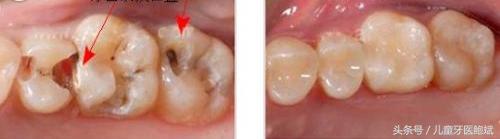

牙齿缝隙大给我们带来的困扰,不止是吃饭塞牙,引发负面情绪。口腔不洁是生成蛀牙和牙周病的主要原因,牙缝间的食物残留清理不干净,时间长了,在菌斑的作用下会变坏腐败,造成牙齿邻面龋坏,牙缝变黑。

塞在牙缝中的食物,除了让人感觉不舒服外,更大的害处在于它会给牙菌斑提供营养物质。如不及时清除,牙菌斑很容易钙化,变成牙石积聚在牙根部,压迫和刺激牙周,使牙周萎缩和导致龋齿的发生。